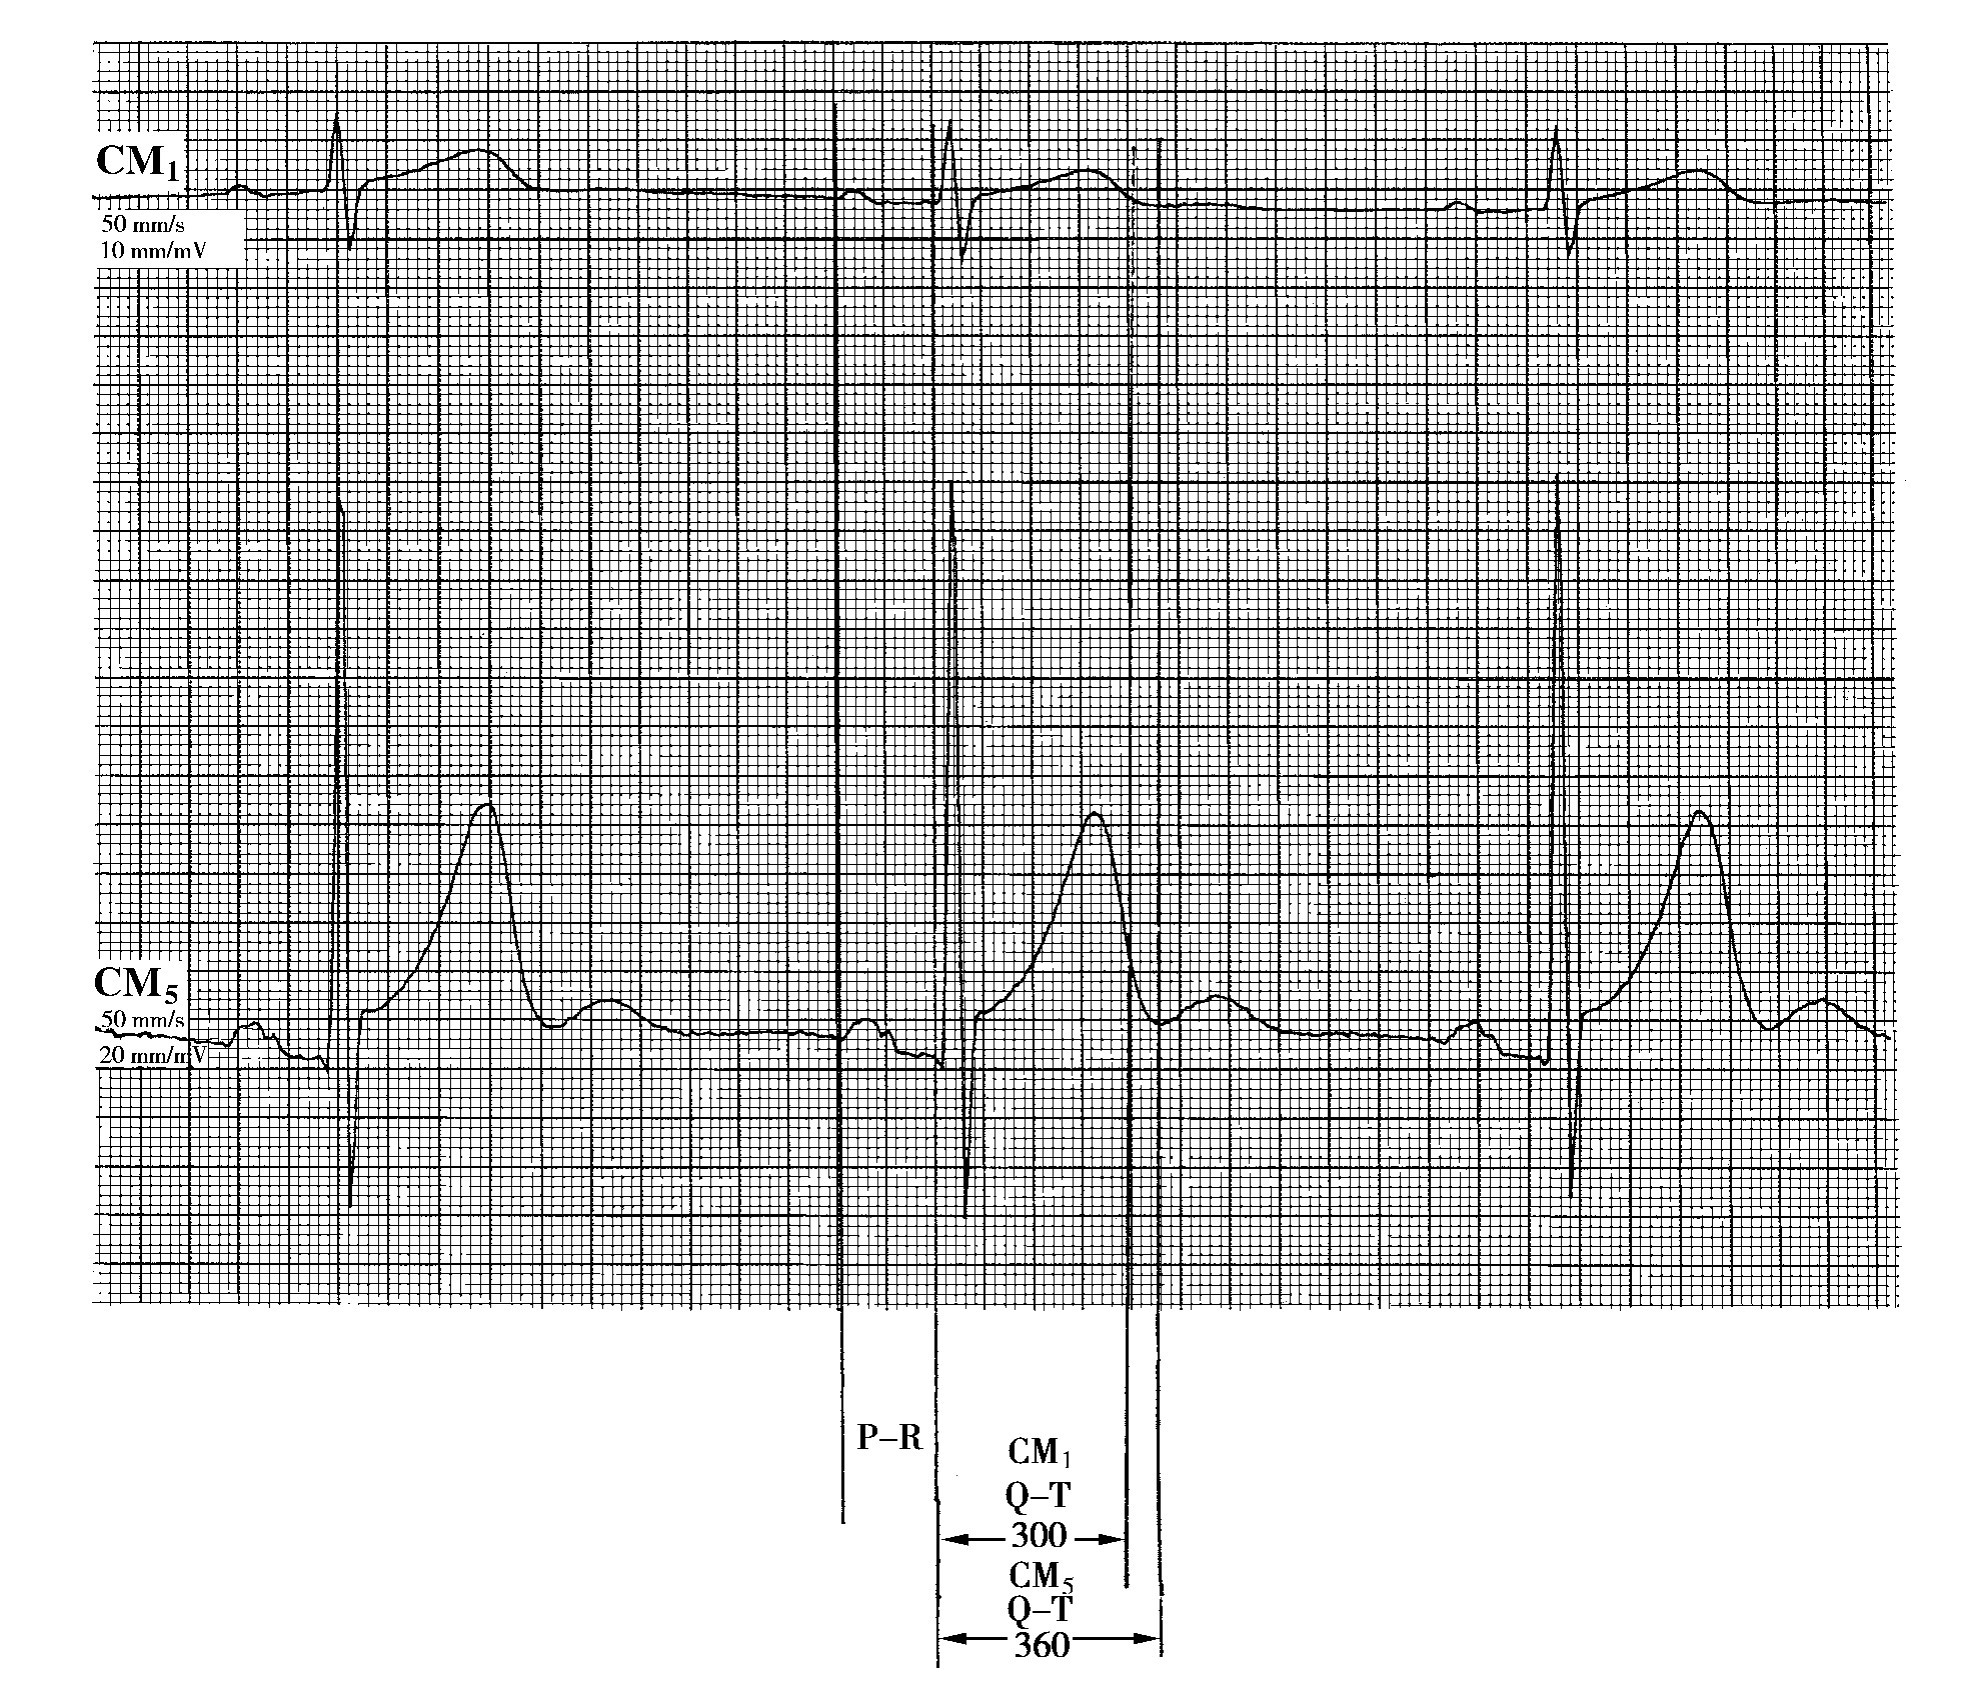

2.Q-T间期离散度 在同步记录的12导联心电图上,最长Q-T间期与最短Q-T间期的差值,称为Q-T间期离散度(QTd)。这是近年来发展起来的评价心室复极离散程度的指标(图7-2)。国内以何秉贤教授为代表的专家认为此种测量方法不妥。

图7-2 Q-Td的测量方法

Q-Td=60ms

正由于上述原因,所以在12导联同步心电图上测量某一波的时限时,应以该波最早出现的导联的起始时点为起点,以最晚结束的导联的结束点为终点,这样的起点与终点之间的时间,才能大致代表这一波的时限(图7-3)。由此推测,以前文献上所指的QT离散度实际上与QRS环在各导联上的投影角度有关。

图7-3 12导联同步心电图测量方法